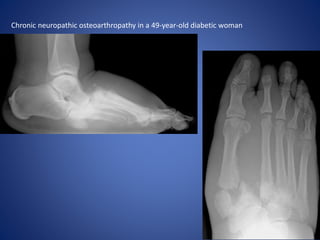

Chronic neuropathic osteoarthropathy has a less inflammatory

appearance, with less visible swelling and less marked edema and

enhancement at MR imaging.

The bones may appear sclerotic at radiography, and they have low

marrow signal intensity at MR imaging regardless of the pulse

sequence used.

Subchondral cysts are well defined, and proliferative bone may be

seen with debris, intraarticular bodies, and ankylosis. Joint

subluxation or dislocation is common due to subchondral collapse,

with resultant articular instability in later stages of the disease

process.

Chronic neuropathic osteoarthropathy in a 49-year-old diabetic woman

Chronic neuropathic osteoarthropathyhas a less inflammatory appearance, with less visible swelling and less marked edema and enhancement at MR imaging. The bones may appear sclerotic at radiography, and they have low marrow signal intensity at MR imaging regardless of the pulse sequence used. Subchondral cysts are well defined, and proliferative bone may be seen with debris, intraarticular bodies, and ankylosis. Joint subluxation or dislocation is common due to subchondral collapse, with resultant articular instability in later stages of the disease process.

Chronic neuropathic osteoarthropathyin a 49-year-old diabetic woman

• #30 Lateral (a) and dorsoplantar (b) weight-bearing radiographs of the right midfoot demonstrate the classic features of neuropathic osteoarthropathy: debris, disorganization, dislocation, osteosclerosis, and destruction of the Lisfranc joints. In a, a fixed rocker-bottom deformity due to arch collapse is seen.